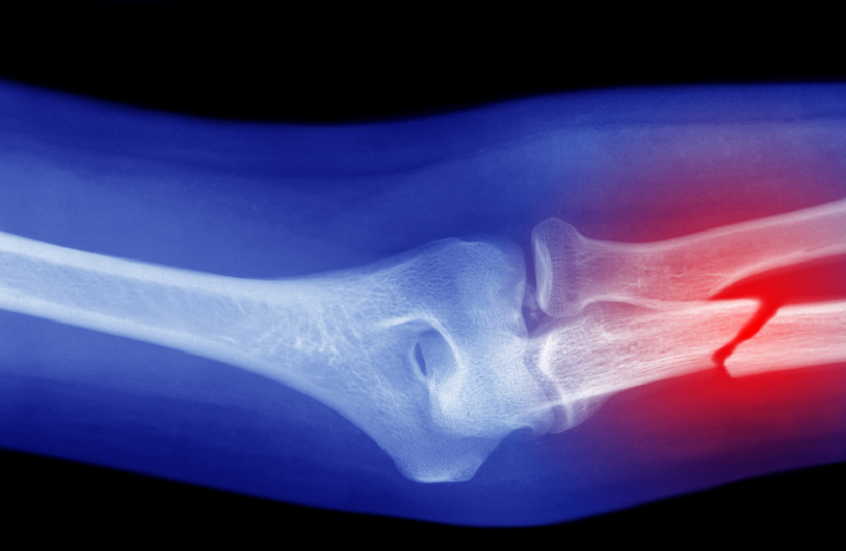

حمية غذائية تقلل من خطر كسور العظام

أظهرت دراسة أجراها علماء من جامعة تشيستر البريطانية أن اتباع حمية البحر الأبيض المتوسط قد يقلل من خطر التعرض لكسور العظام.

قام العلماء أثناء الدراسة بمراجعة بيانات وإحصائيات لـ 30 دراسة سابقة، شملت أكثر من 500 ألف شخص بالغ، وقارنوا بين تأثير حميات غذائية شهيرة على صحة العظام، وهي: حمية البحر الأبيض المتوسط، والحميات منخفضة السعرات، والحميات عالية البروتين، والمنخفضة الكربوهيدرات، وحمية الكيتو.

وأظهرت النتائج أن كثافة العظام لم تتغير بشكل كبير بين معظم متبعي هذه الحميات، ولكن الفوارق كانت مرتبطة بمعدلات الكسور؛ حيث وجد الباحثون أن الأشخاص المتبعين لحمية البحر الأبيض المتوسط كانوا أقل عرضة للإصابة بالكسور، بما في ذلك كسور الورك.

على النقيض من ذلك، ارتبط التقييد الحاد للسعرات الحرارية بارتفاع مؤشرات تدمير بنية العظام، ما يعني أن هذه الحميات قد تضعف العظام على المدى الطويل.

يرى الباحثون أن التأثير الوقائي لحمية البحر الأبيض المتوسط يعود إلى محتواها الغني بالعناصر الغذائية، فهي تعتمد على الخضروات، والفواكه، والأسماك، والحبوب الكاملة، والبقوليات، وزيت الزيتون، وهذه الأطعمة تزود الجسم بالكالسيوم، والمغنيسيوم، وفيتامين K، وهي عناصر مهمة للحفاظ على العظام وتجدد خلاياها، أما بالنسبة للأنظمة الغذائية القاسية التي تهدف لخفض الوزن بسرعة، فقد تؤدي إلى خلل في توازن هذه العناصر المهمة، مما يسرع من عملية هدم الأنسجة العظمية.